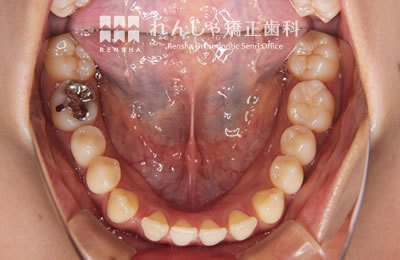

大きながたつきを歯列の拡大で改善しようとすると歯周組織へのダメージや後戻りが問題になります。この様な場合はスペースを確保するために永久歯を抜歯する方法を選択します。歯を抜いてしまうことに不安もあるかと思いますが、抜歯矯正が長い目で見たときにいい結果になることも多いと思います。

治療前

| 主訴 | 叢生 |

|---|---|

| 診断名 | Angle Class I 叢生 |

| 初診時年齢 | 27歳0か月 |

| 装置名 | マルチブラケット装置 |

| 抜歯非抜歯 | 上下顎左右第一小臼歯の抜歯(合計4本) |

| 治療期間 | 2年5か月 |

| 費用の目安 | 約93万円+消費税(検査料金、都度の処置費用等も合わせた総額) |

| リスク副作用 | 歯の移動に伴う軽微な歯根吸収、歯槽骨吸収、歯肉退縮(本症例では軽度の歯肉退縮を認めた)、矯正器具装着中のカリエスリスク増大(本症例ではカリエス発生無し) |